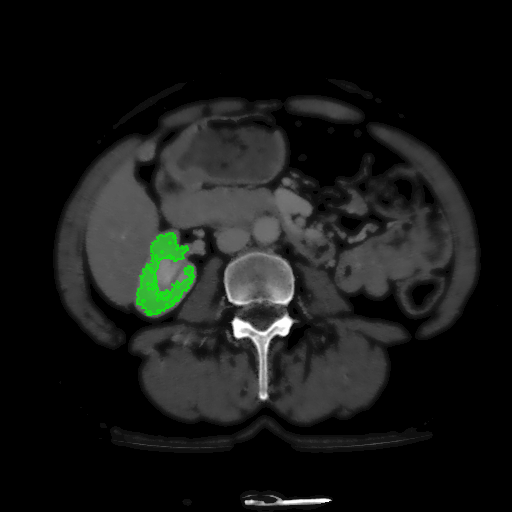

For MSER tracking, Donoser and Bischof [5] presented three different applications; license plate tracking, face tracking and the segmentation of a fiber network. In the third application, a fiber network is reconstructed in 3D by tracking a slice of the data along the axis orthogonal to the image data. Analogously, we track organs in slices of a Computed Tomography (CT) scan, to generate a 3D segmentation. We use the CT data provided in the 3DIRCADb dataset222The dataset is available on http://ircad.fr/research/3d-ircadb-01 [14].

To initialize the tracking process, the organ is segmented in an arbitrary slice of the CT data by a bounding box. The most stable MSHR is then selected in the initialization process for tracking. The respective MSHR is tracked through the slice data along the axis orthogonal to the image data. An example of the tracked regions is visualized for two examples in Fig. 7. Given the segmentations of the single slices, the organ can be reconstructed in 3D. We compare the reconstruction for MSER and MSHR tracking in Fig. 8. To enhance the visualization, the datapoints are triangulated and the surface normals calculated. Since the contrast of the organs can be very low in CT images, the MSER tracking has difficulties catching the organ boundaries. Furthermore, the organ is sometimes partely lighter and darker than the background, which may lead to MSER tracking failure. The proposed MSHR tracking copes well with these difficulties, and the reconstructions are significantly better.

Figure 7: Two examples sequences from the 3DIRCADb dataset [14]. Given an initial selection of a single slice (the middle image in (a) and (b)) of the organ, the proposed MSHR tracking tracks the region forward and backwards in space. The segmented slices can be used to reconstruct the organ, see Fig. 8 for an example reconstruction.